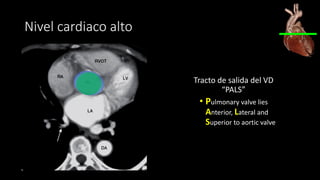

Nivel cardiaco alto

Tracto de salida del VD

“PALS”

• Pulmonary valve lies

Anterior, Lateral and

Superior to aortic valve